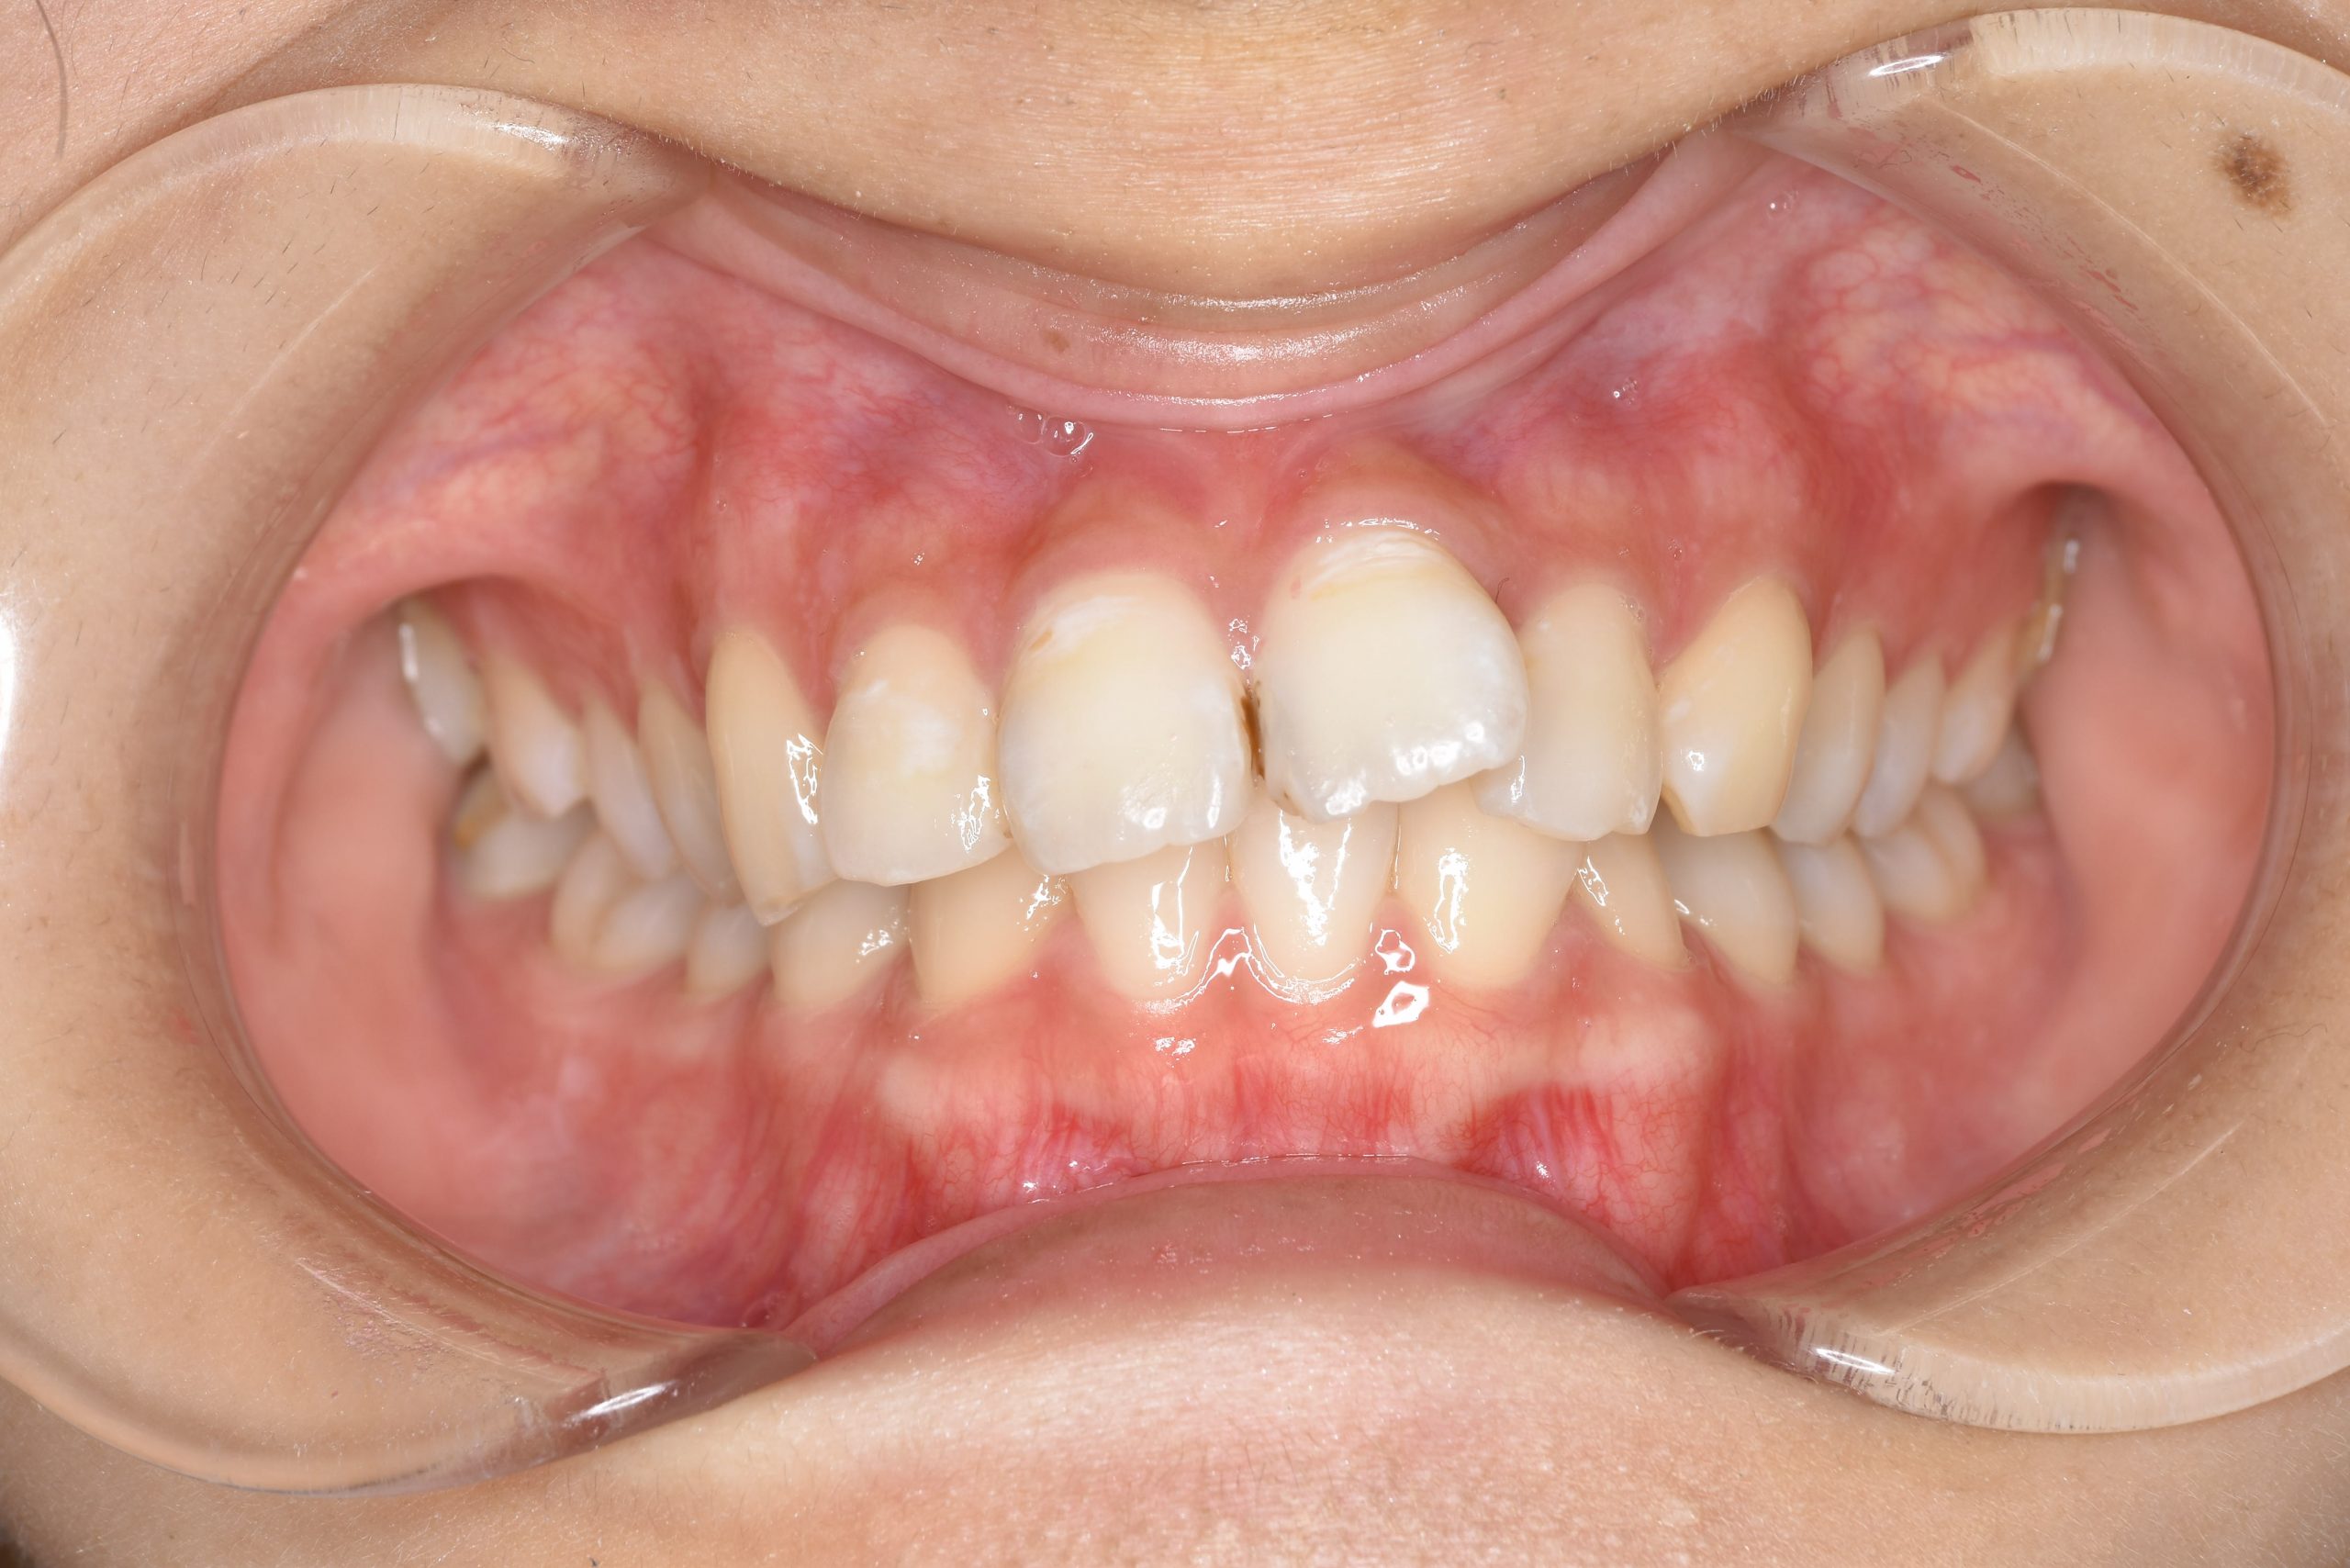

ビフォー

主訴 出っ歯

施術内容 MSEと下顎リンガルアーチを用いて上下顎骨を拡大した。

その後マルチブラケット装置とミニインプラントを用いて非抜歯で歯牙を配列した。

下顎前歯が1本先天性欠損であったが、良好な咬合を獲得した。口元の突出感と鼻閉症状は改善された。